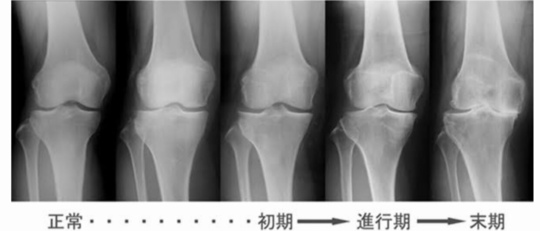

年齢・進行と変形性膝関節症

形性膝関節症の初期は4050代ではじまり、歳を重ねていくごとに変形は進行していきます。

痛みを繰り返すから骨はどんどん変形していき、最終的には末期の変形になります。